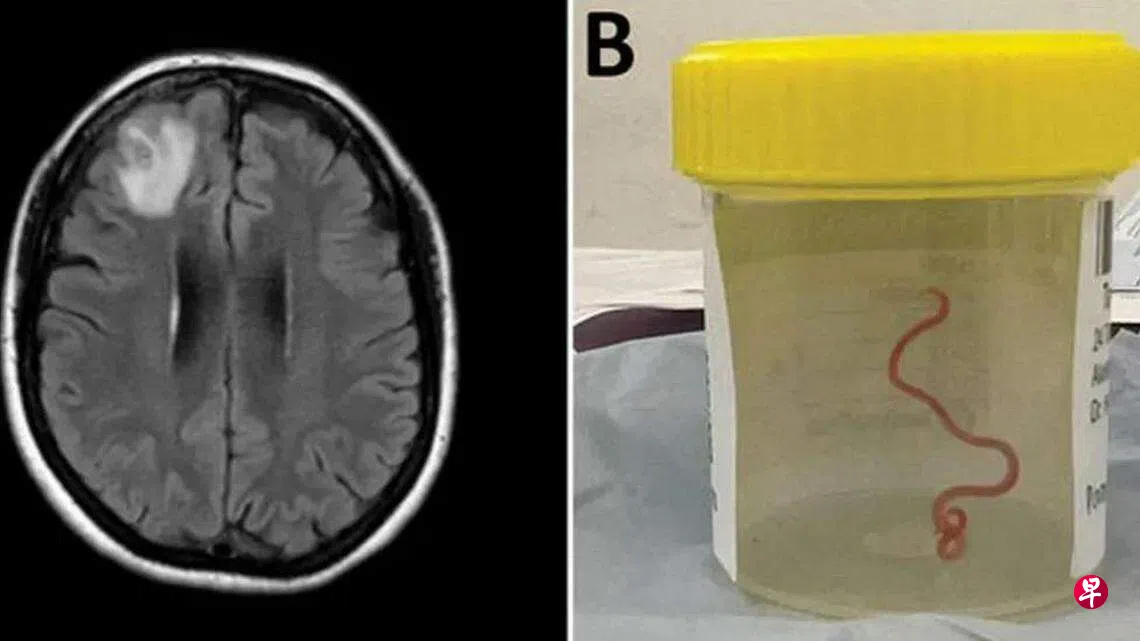

2022年,她的症状还包括健忘与忧郁,因此转院到堪培拉的医院就医。经磁共振成像(MRI)扫描后,医生发现她的脑部异常,必须动手术,结果医生从她脑中拉出一条八公分长的蛇蛔虫(Ophidascaris robertsi),这是人类遭蛇蛔虫侵入的全球首例。